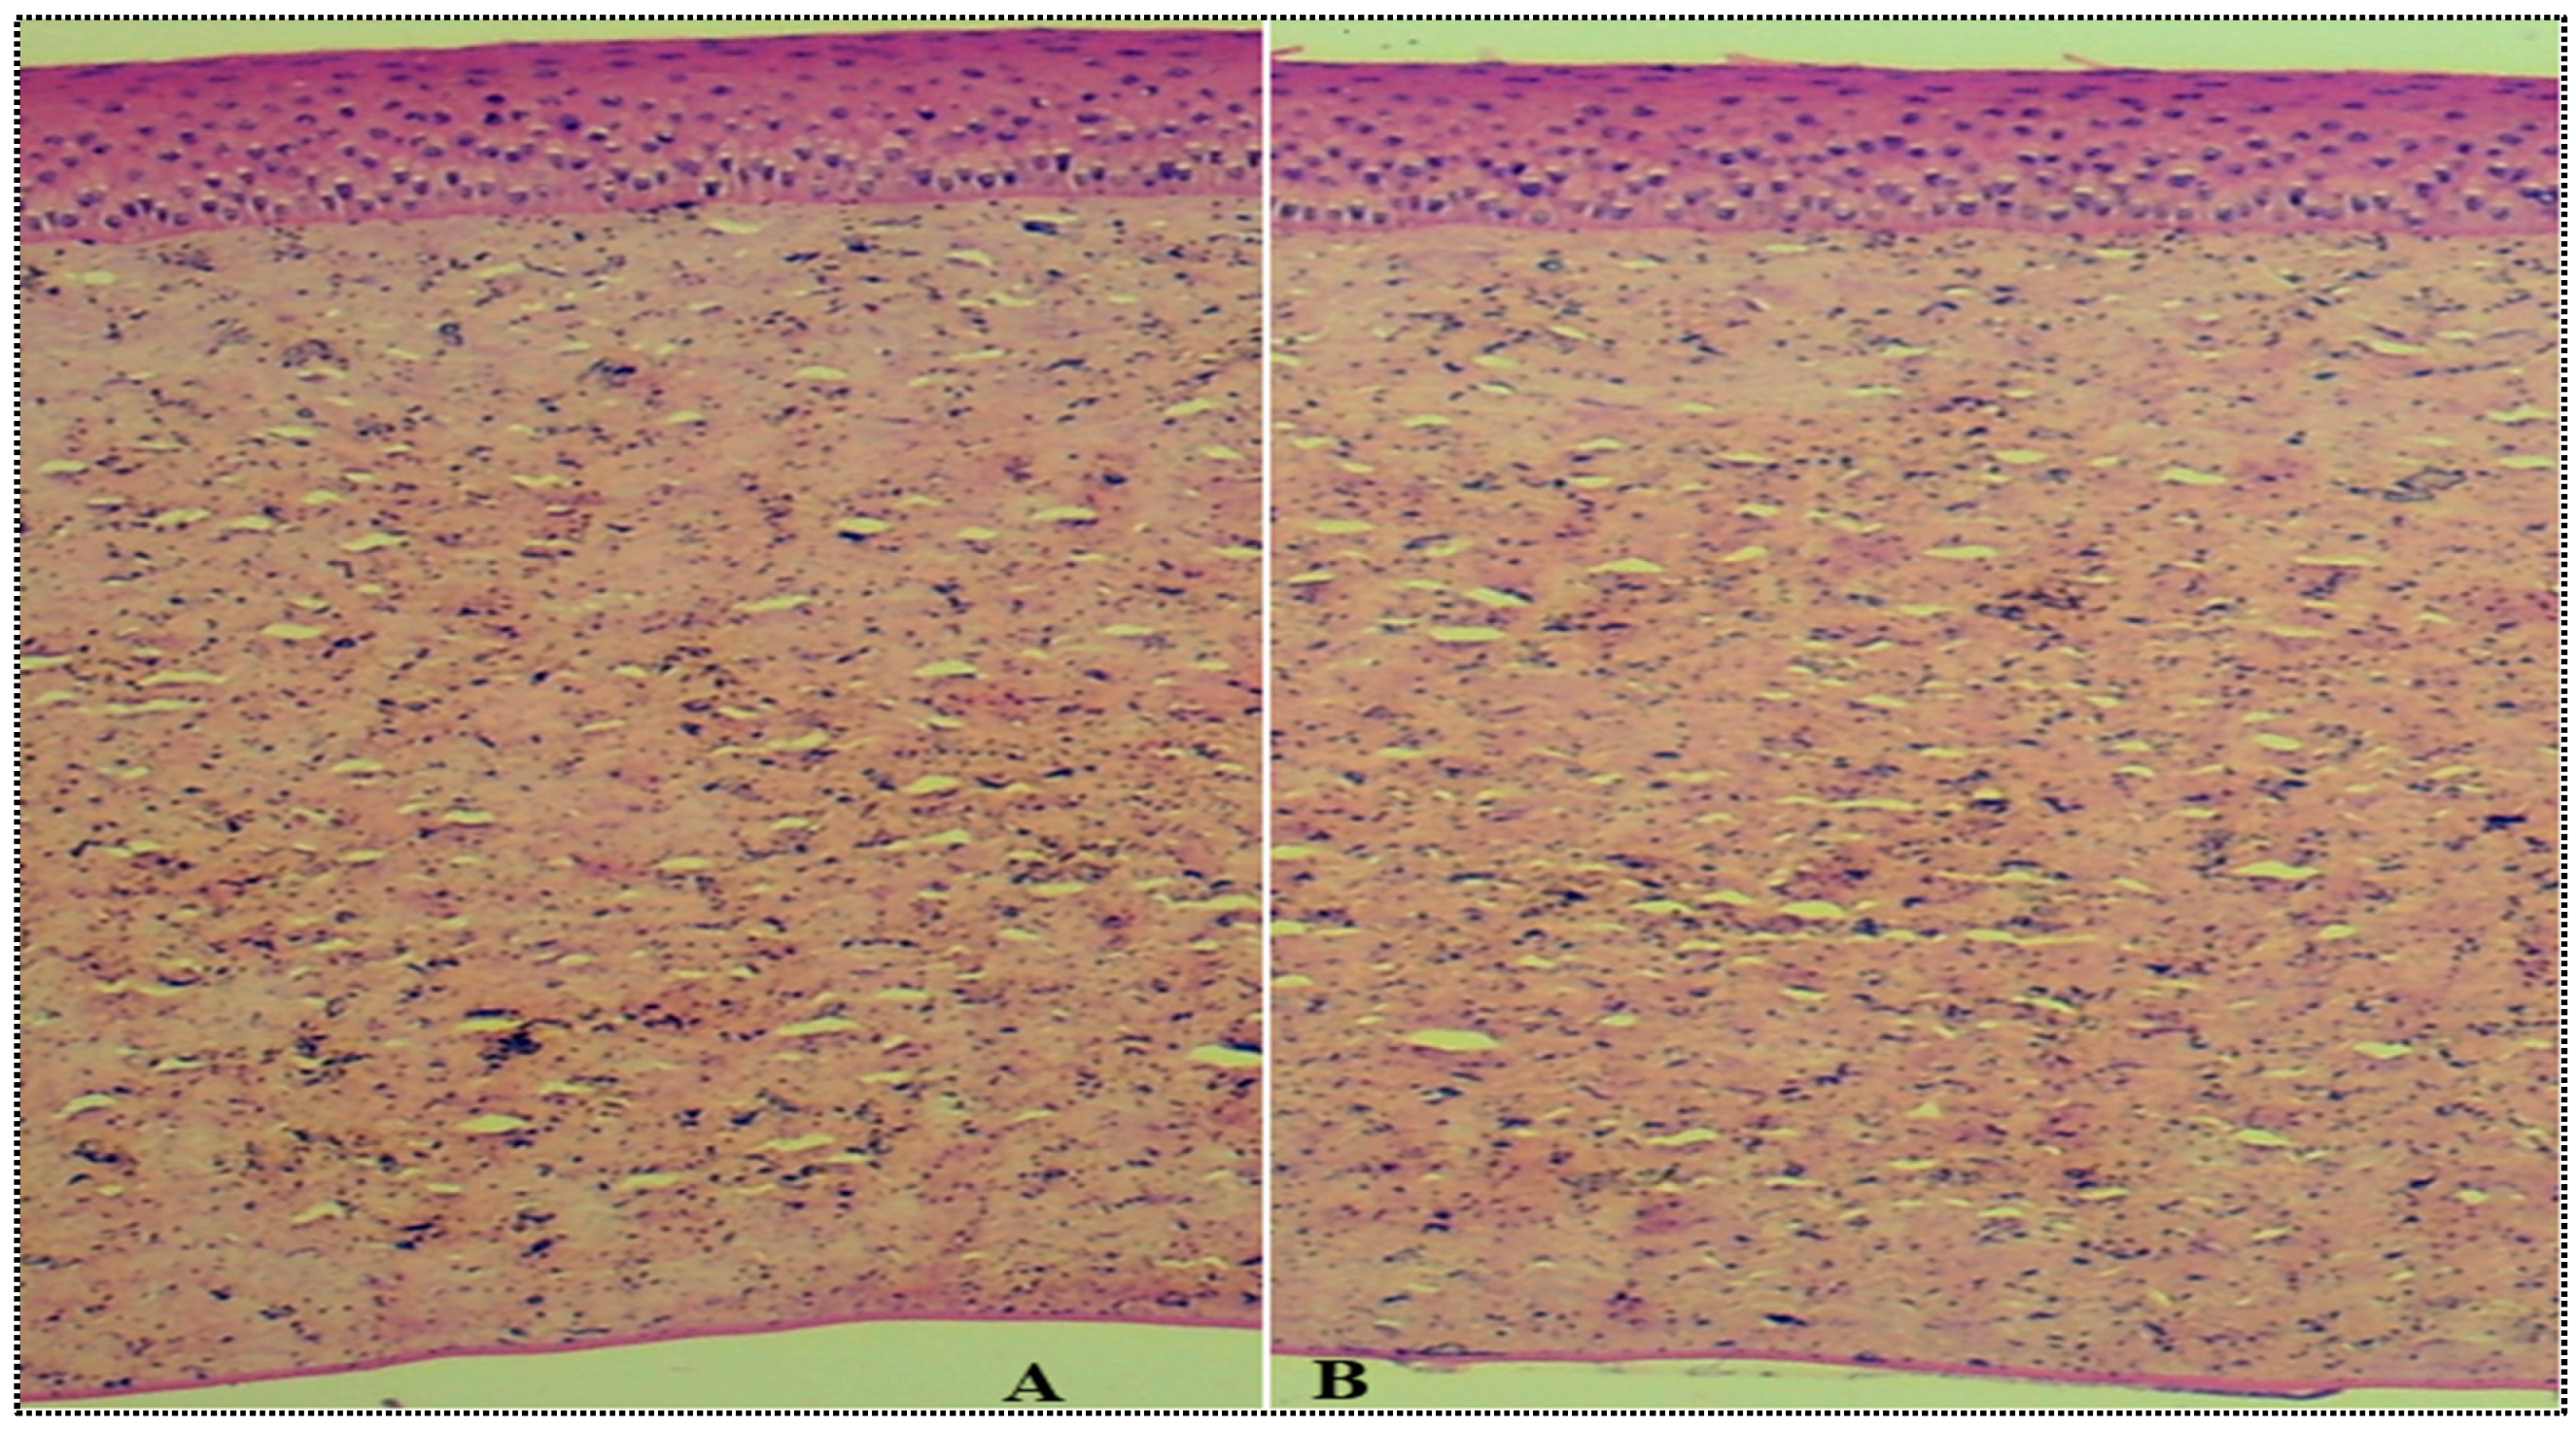

2.4.7. Histopathological Study

4.4.7. Histopathological Study